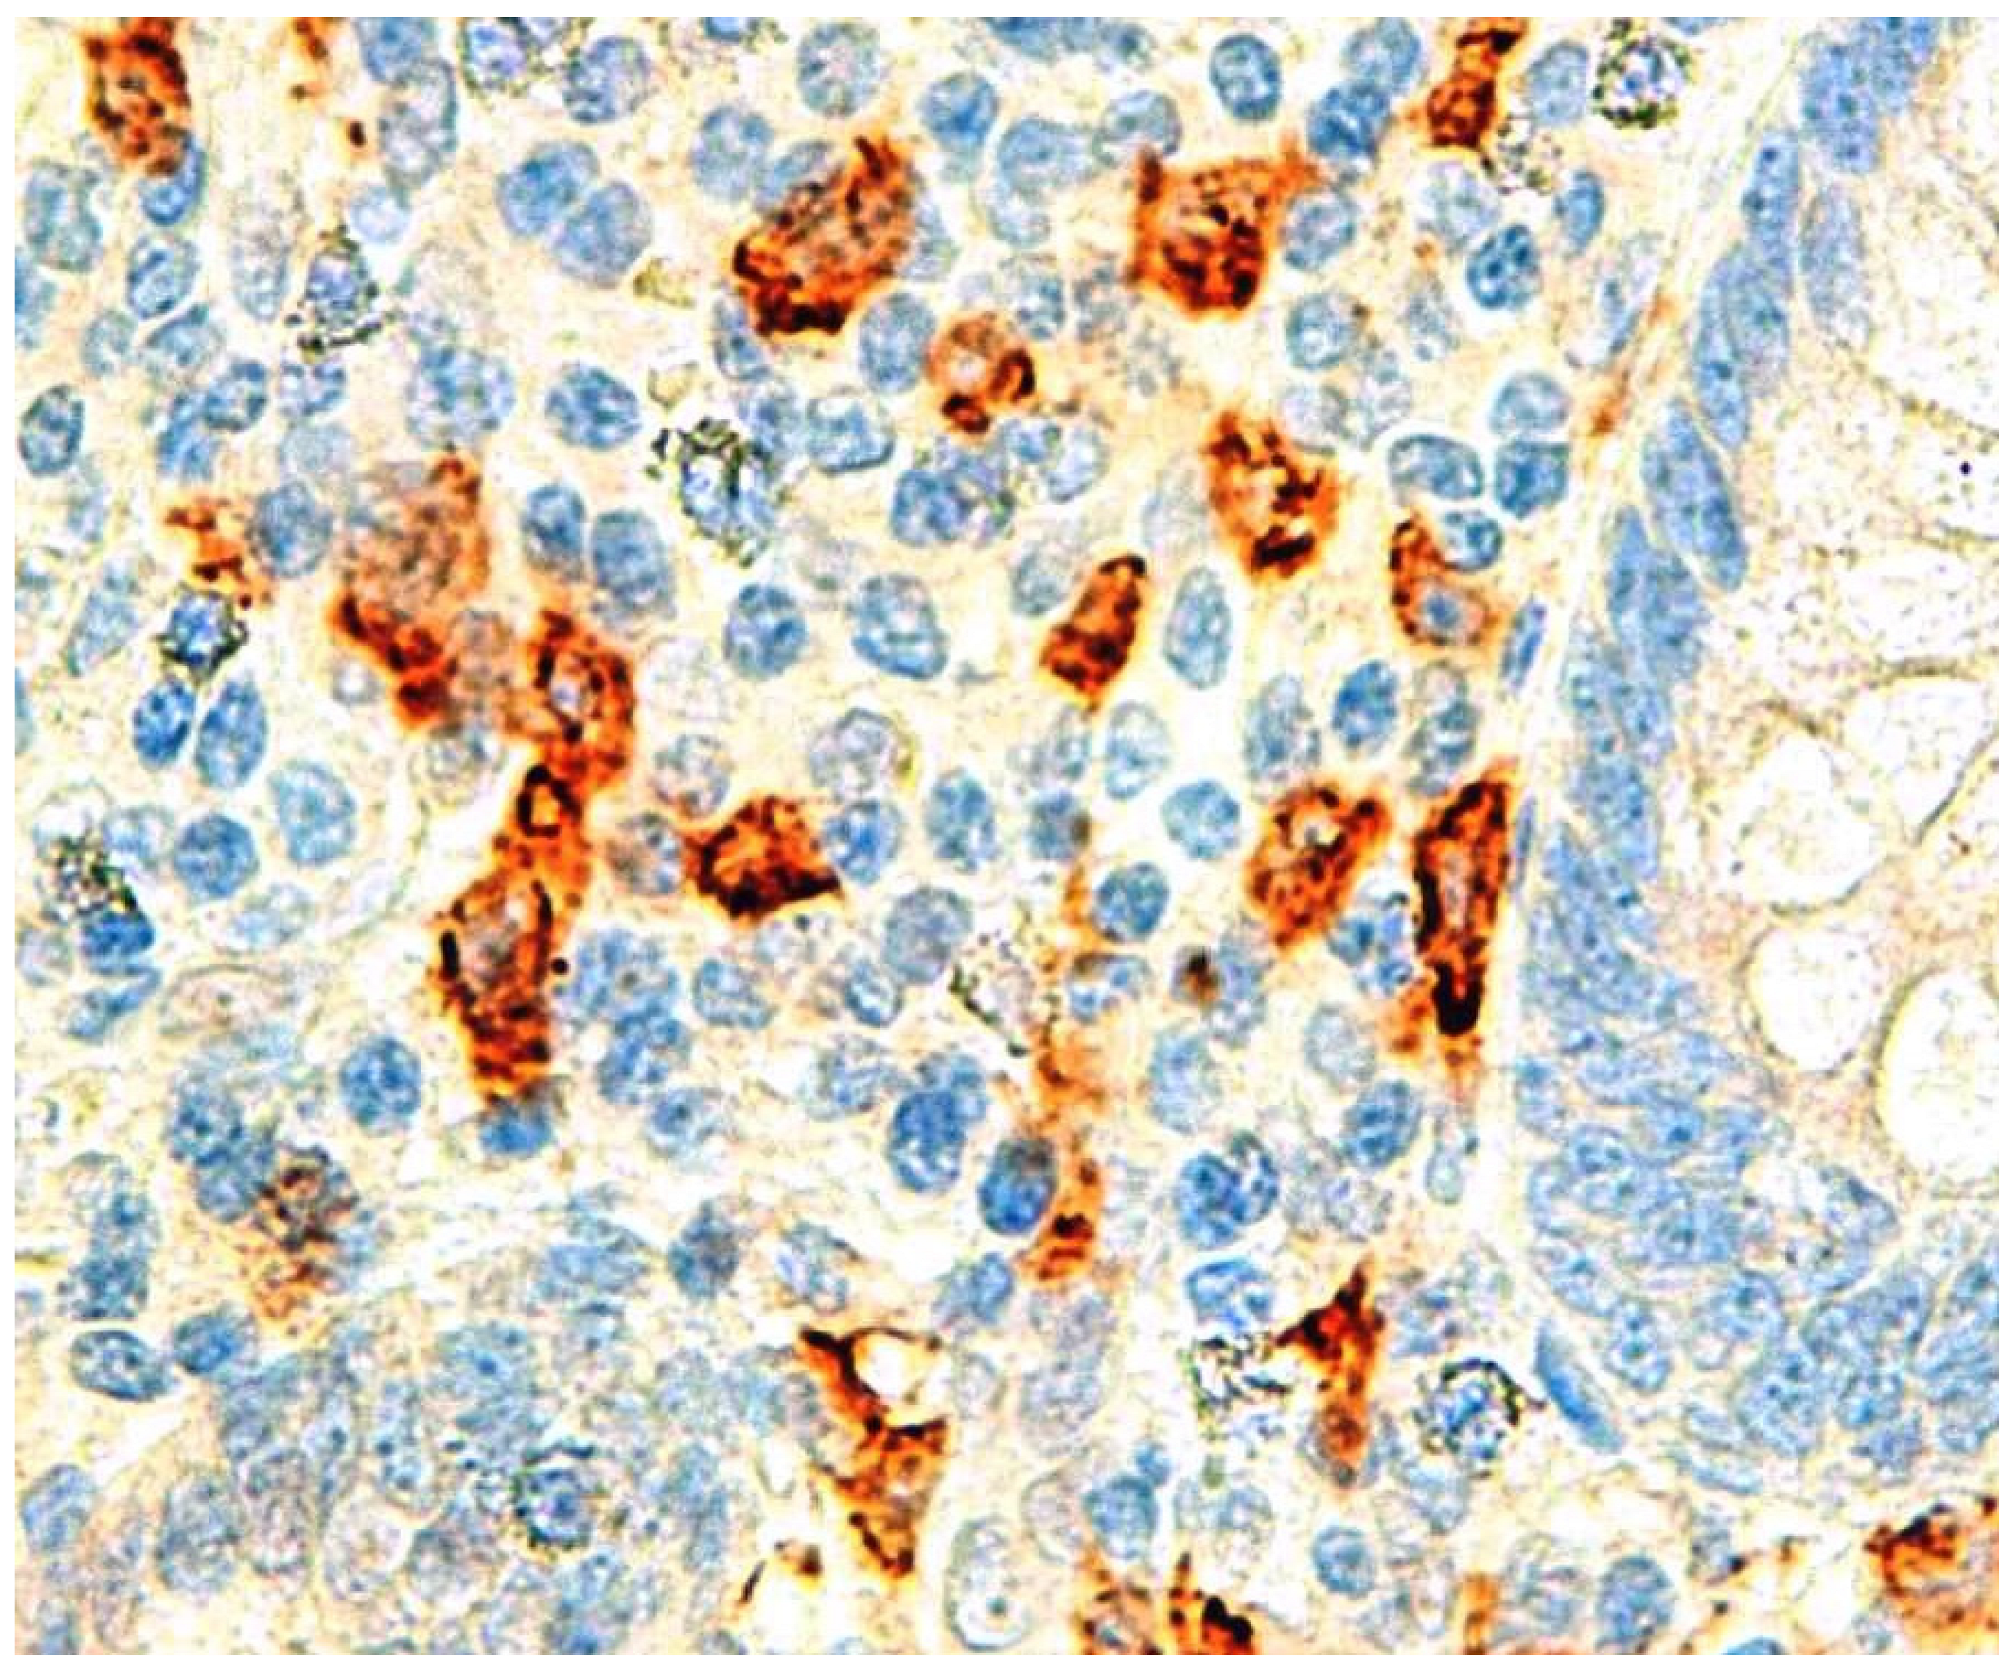

- Carvalho, N.; Barros, A.; Coelho, H.; Cóias, A.; Botelho, P.; Cismasiu, B.; Moita, L.; Costa, P. Increased IgE Deposition in Appendicular Tissue Specimens Is Compatible with a Type I Hypersensitivity Reaction in Acute Appendicitis. Mediat. Inflamm. 2021, 2021, 4194859. [Google Scholar] [CrossRef]

| Appendicular wall IgE | Carvalho N [50] | Retrospective | IgE positive cells higher in phlegmonous AA |